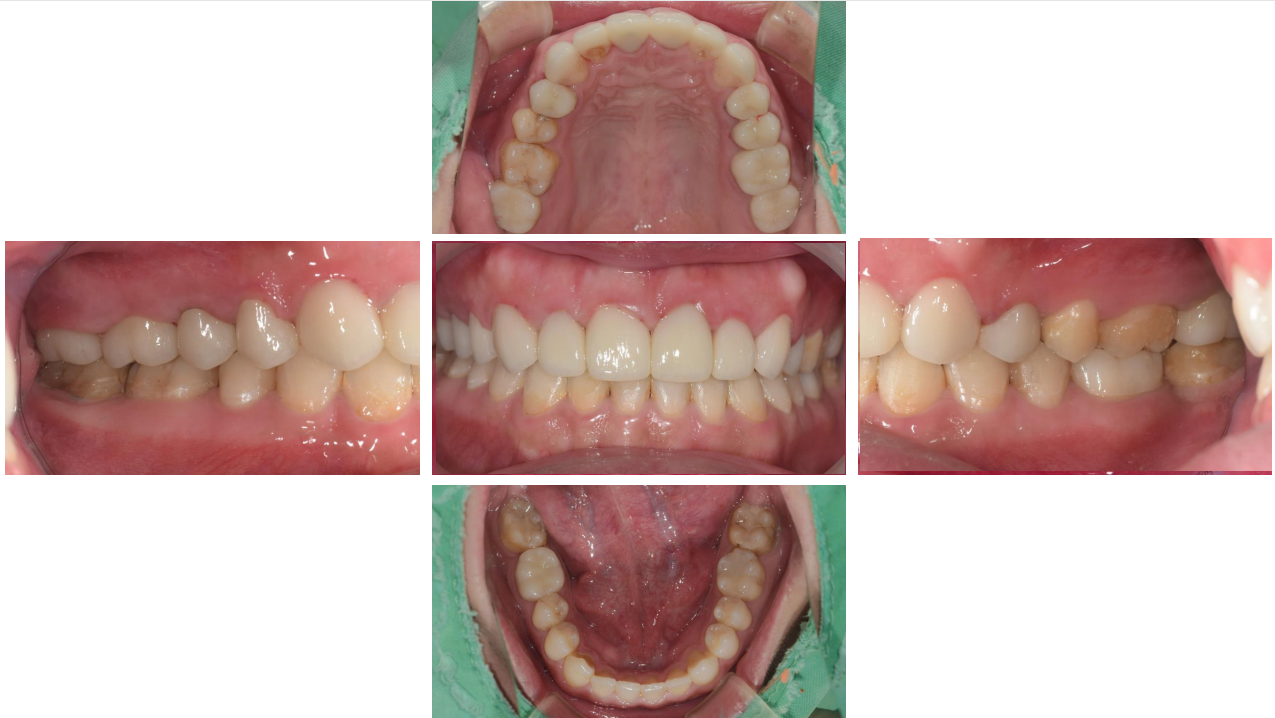

治療前 :前牙錯咬,上下排齒列不整,蛀洞大,左下缺牙空間大。

治療後 :左下缺牙空間靠矯正成功關起來,齒列整齊,前牙調整至正確咬合位置。